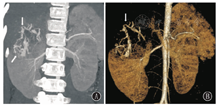

CT平扫上可见肿瘤呈不均匀等/低于肌肉密度,其中3例肿瘤于中心区域可观察到斑片样低密度区,2例低密度区呈小灶状或条片状散在分布,增强后不强化或仅呈轻度强化,CT值升高均<10 HU,病变周围部分可见动脉期明显强化,CT值升高约30~79 HU,静脉期呈持续强化,CT值继续升高8~36 HU,2例肾脏病变者加做了延迟期扫描,可见病变周围部分有强化减低表现,1例出现向心性强化(图1)。1例病变平扫密度较均匀,未观察到明显密度减低区,增强后病灶仍以周边强化为主,CT值升高约52 HU,中心区域轻度强化(CT值升高约17 HU)呈相对低密度区。5例肿瘤内可见迂曲增粗血管影,且多分布在肿瘤周边部分(图2)。2例病灶内可见点状及沙砾样钙化。

在增强CT图像中,PEComa常在动脉期表现出周边分布的明显强化,这表明PEComa是一种富血管性肿瘤,且供血微血管常围绕肿瘤周围存在,这一"周边强化"的影像学特征可能对PEComa的鉴别诊断很有价值[3,11]。由于病变内拥有多种不同的细胞成分,故多呈不均匀强化,5例肿瘤中心的低密度不强化区代表了瘤内的大面积坏死、液化部分,其中3例肿瘤切除后得到了病理证实。1例病变平扫密度较均匀,增强后仍以周边强化为主,中心区域轻度强化呈相对低密度区,可能与其平滑肌结构或其他少血管成分有关。对本组病例的CT动脉期图像进行最大密度投影(MIP)重建可清晰显示肿瘤内迂曲增粗的血管,可见5例PEComa的血管分布于病变边缘,呈包绕状,这与大多数肿瘤血管常延伸至病变内有所不同。静脉期多数PEComa在静脉期呈持续强化,延迟期病变周围部分出现强化减低,1例病变出现类似"血管瘤"的向心性强化,更说明了该病变血供丰富。